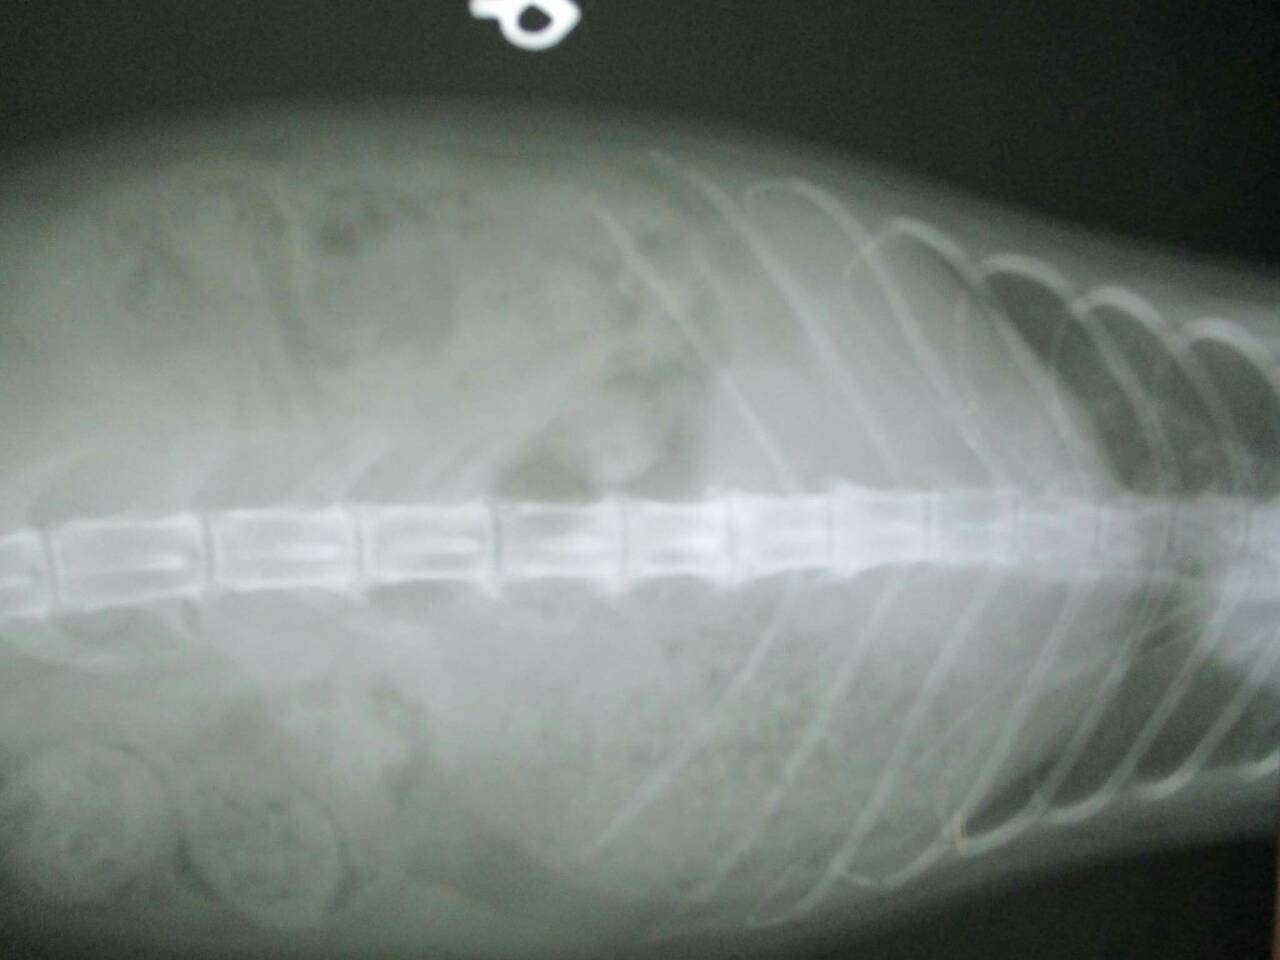

主題: 壽山收容所 背傷癱瘓貓 申請者姓名: 劉素鳳 花色: 申請日期: 2016-02-02 23:46:43 申請者部落格: 申請者臉書網址: https://m.facebook.com/sufeng.liu?ref=bookmarks 所在縣市/合作醫院: 高雄市/樂生動物醫院 治療費用: 3200元 需求人數: 8人 已結案 (2024-06-01 13:41:09) 報名人員: Freesia Tsai(已付款)、Amber Chung x2(已付款)、兔子(已付款)、karena(已付款)、Nancy Wu(已付款)、Tina Chen(已付款)、吳金英(已付款)、 候補人員: 動物病情說明: 壽山收容所專案的貓咪,這隻三花貓小刀 原本背部傷口有在癒合了,但在前一家醫院觀察後發現他後軀的神經反射有問題,後腳目前是都無法站,而且有點癱瘓的狀況,只能靠前肢撐著。

醫生初步檢查左邊腸薦關節有做手術,胸腰椎交接處(T13~L1)有受傷,可能是造成後驅癱瘓的主因,左右兩側後腳還有反射但左邊反應較差,傷口部分目前還好並無分泌物但後面幾天還是需觀察,如有分泌物出現則有可能又需做清創手術,血檢並未有異常,貓咪目前食慾還不錯,所以並未上點滴,目前會先就傷口照護為主, 醫生建議貓咪轉到大醫院做針灸的治療,努力應該會有康復的機會, 謝謝大家幫助這貓咪^^ . 、